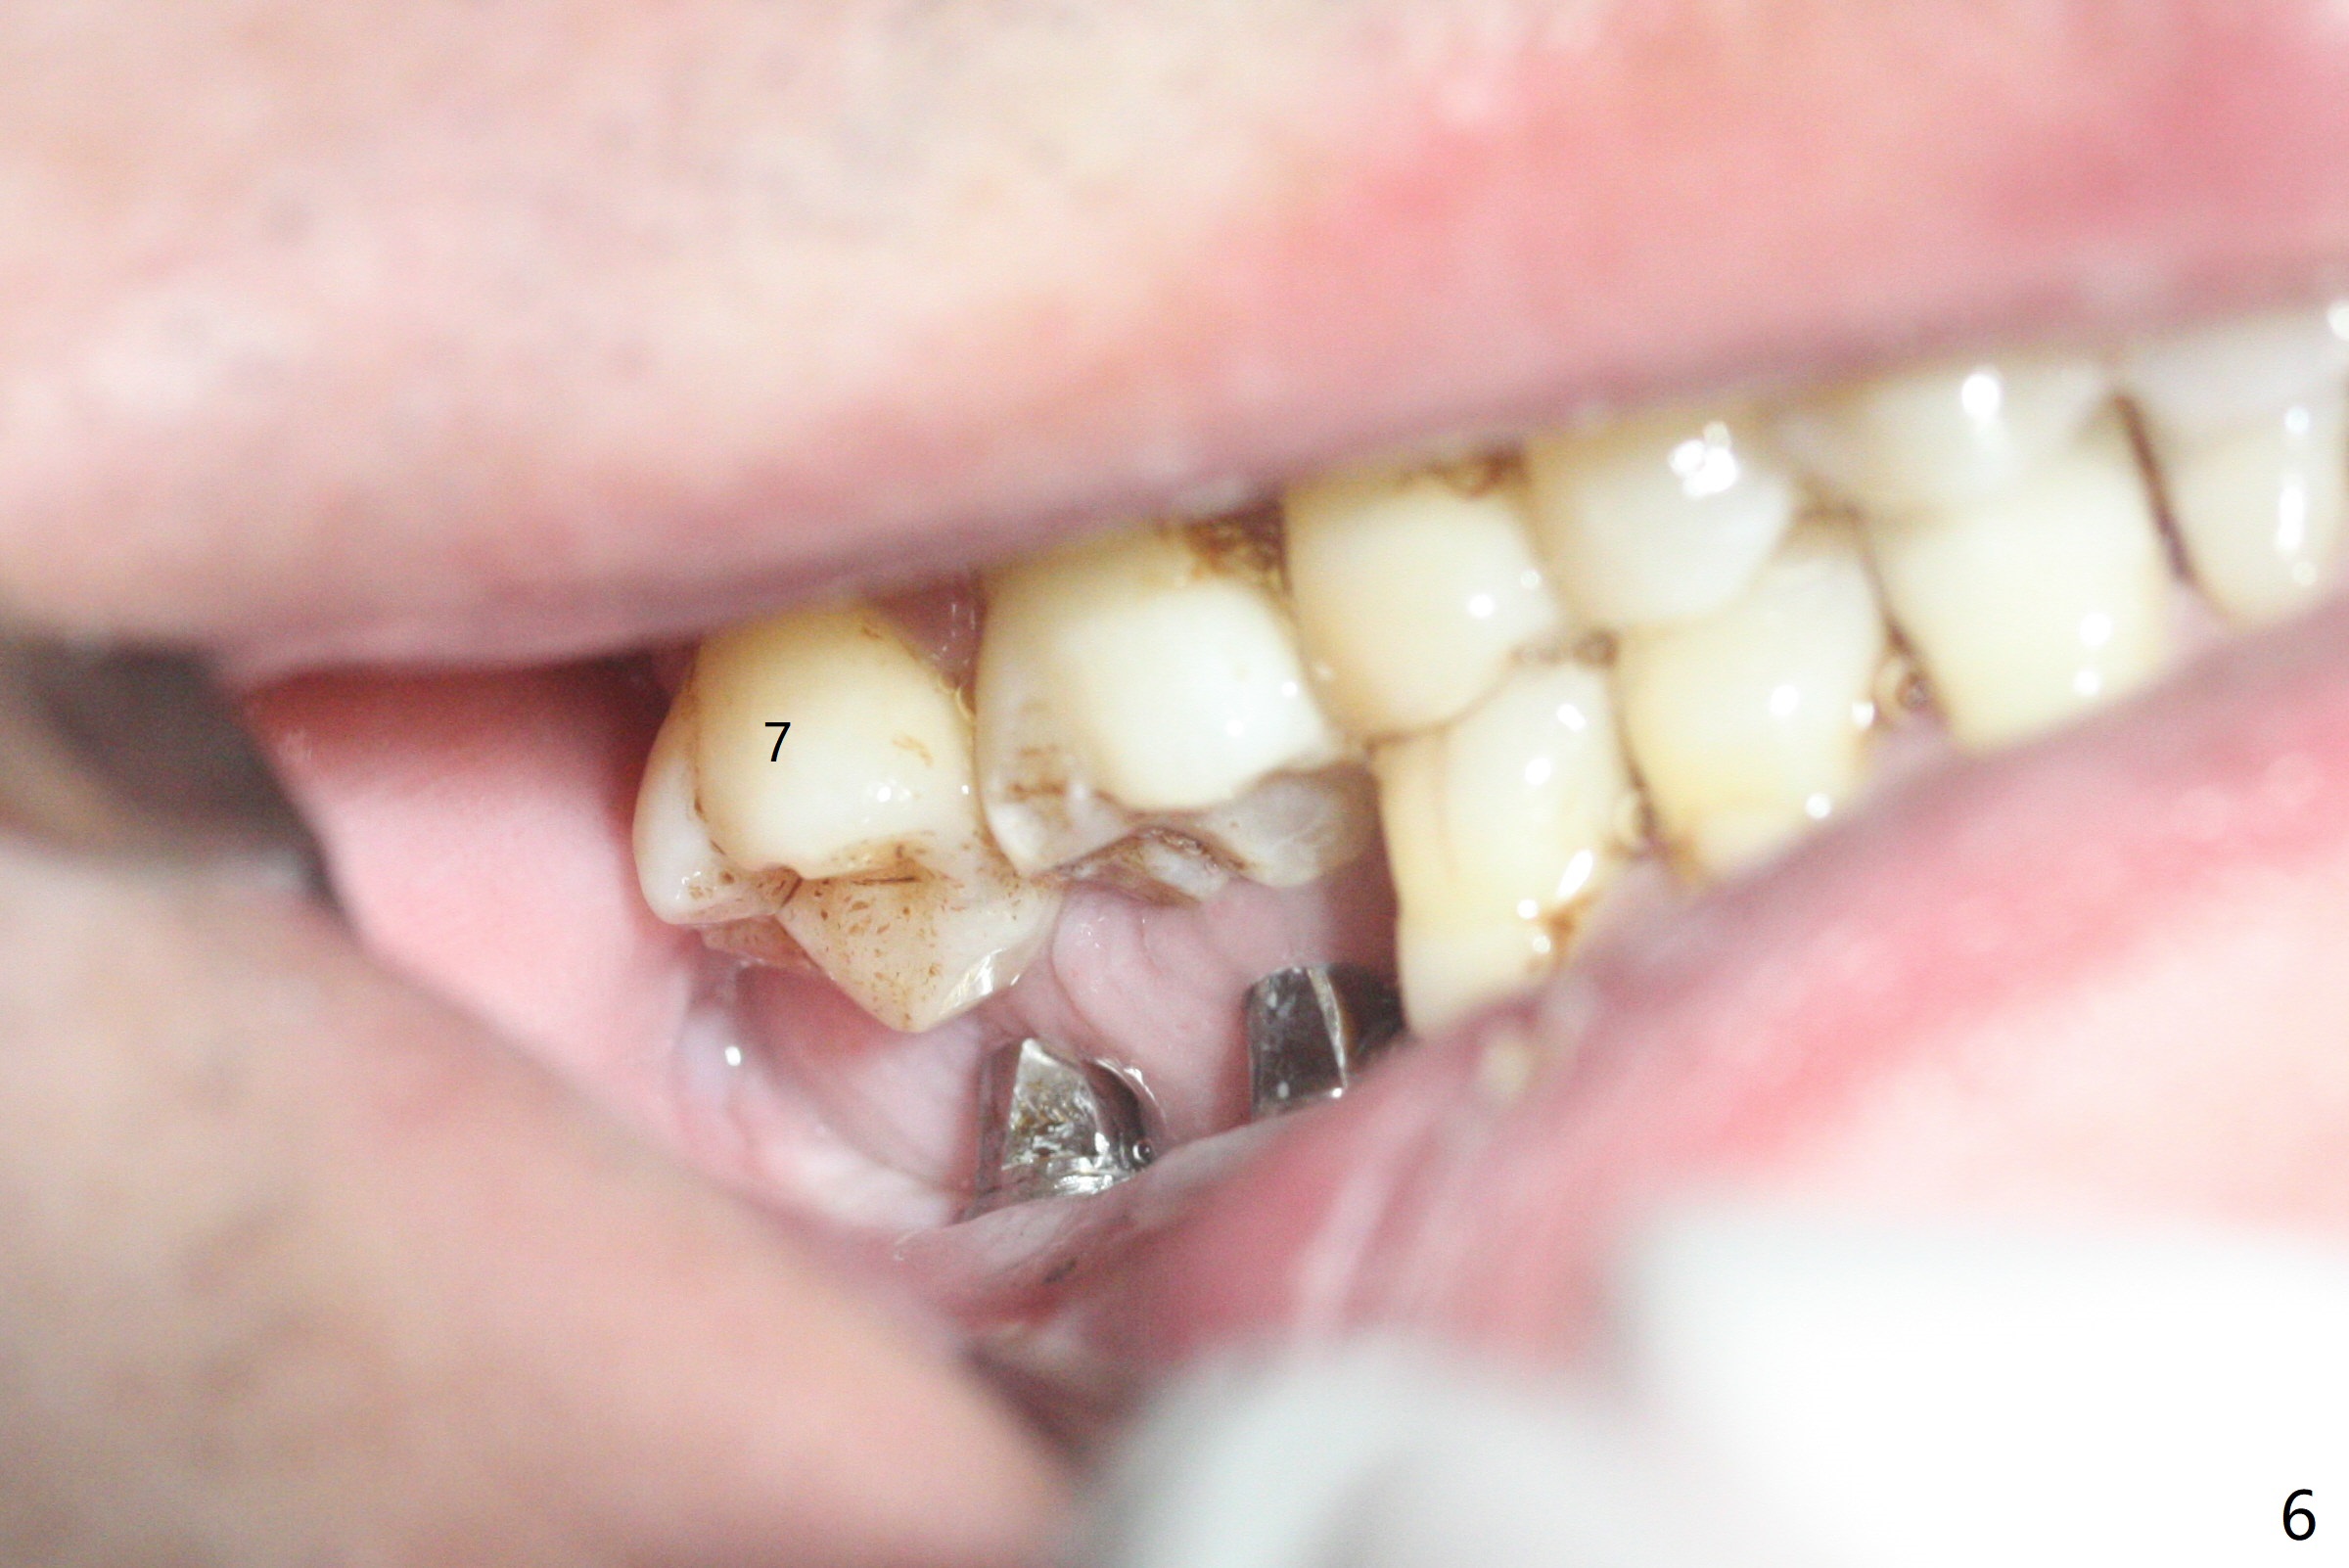

54岁男,右下6,7位点保留后7个月回来植牙,植牙床是个平面(图一),今后两个牙齿之间龈乳头一定缺乏,如何重建?放置导板,稍微使用环形钻头,在6,7植牙床上形成标记(图二),然后切开,植入植体,6扭力低,7高,所以安置愈合(6x5毫米)和修复(5.5x4(4)毫米)基台。原来导板设计把植体植入牙槽嵴(图三:白虚线)下1-2毫米,自动提高植体间牙槽嵴,接着把钻洞产生的骨粉放在后者上缘(*),由近中和远中基台固定。最后覆盖胶原膜,缝合(图四)。原来导板需要切除的角化龈保留住了(图四:7B,7L)。放入修复基台目的是利用它的高度固定牙周敷料。术后3个月7牙槽窝愈合(位点保存后10个月,图五:*),植体间牙槽嵴仍旧高(箭头),6放置修复基台,准备做临时牙冠。右上7反合,需要做局部矫正(图六)。病人非常感激术后三个月制作的临时牙冠(连体)。术后五个月对临时牙冠进行修改:6牙合面垫高(图七:*),这样上下7牙合面分开,上7颊侧放置矫正器,下7牙圈(舌侧有cleat),两者之间安置橡皮筋,上7就可以自由往舌侧移动。术后8.5个月全景片和CT显示植体种植牙槽嵴下(图八至十),这也是重建龈乳头基础。